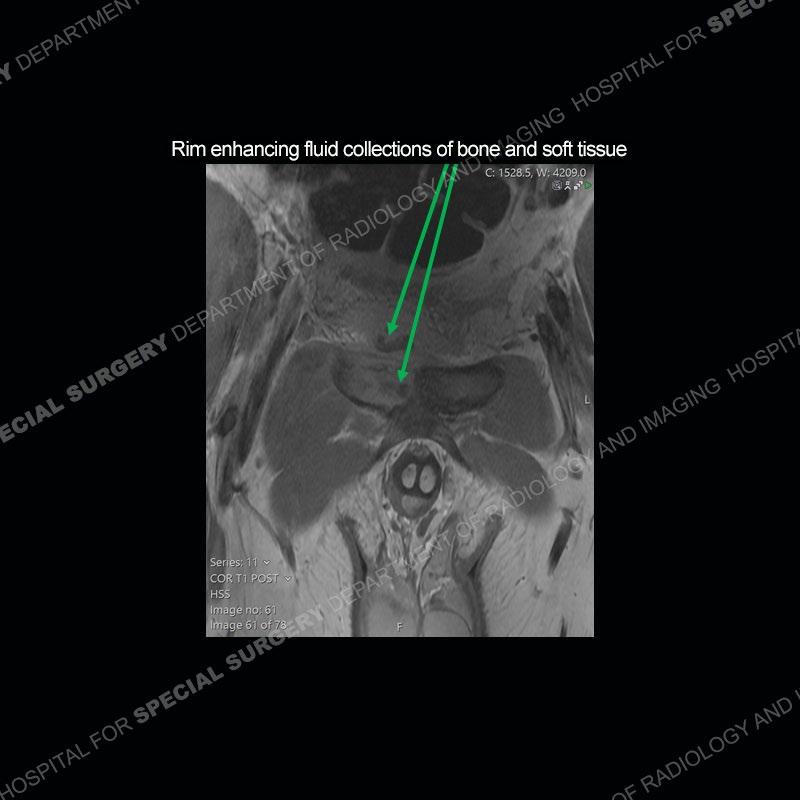

Subsequent MRI in a very short time interval shows markedly increased abnormality of the ramus and increased edema and “mass” of the soft tissue. Post contrast imaging shows multiple, rim enhancing collections of the soft tissue and similar albeit less conspicuous enhancing collection of the ramus.

The repeat MRI, with the marked degree of increased abnormality of the bone and soft tissue shifted the diagnosis to a high degree towards infection. Even the most aggressive of neoplasms would not have that the degree of change in a 3-day time span. The CT study was shown before the repeat MRI but actually occurred just after the repeat MRI. It helped confirm the destructive process of the ramus and particularly the abnormal architecture along the inferior margin. The patient went on to have a CT guided aspiration of one of the soft tissue collections with 4cc of purulent fluid obtained. A surgical irrigation and debridement of the bone and soft tissue was performed. A PICC line was placed and the patient is currently undergoing IV antibiotic treatment with a possible repeat irrigation and debridement.